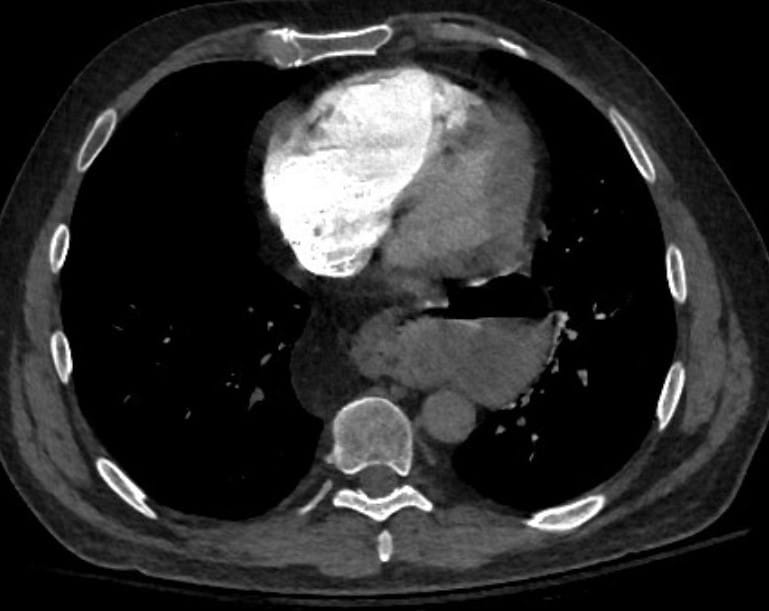

A saddle PE is a pulmonary embolism that is located over the main pulmonary arteries. Perhaps surprisingly, many patients do not have symptoms. In fact, many had imaging for another reason and the PE was an incidental finding. However, sometimes these central clots block cardiac outflow enough to cause syncope, acute right heart failure and even death.

In medical practice finding a saddle PE sometimes results in concern. The name itself seems to invoke respect by many clinicians. Of course, any proximal pulmonary embolism is a reason for concern. But it actually turns out that the location of the clot has little relationship with patient outcomes. In fact, many patients with saddle PE are asymptomatic. Having said that, this is not always the case. Sometimes the PE causes acute right ventricle failure. This can result in acute syncope and even in death.